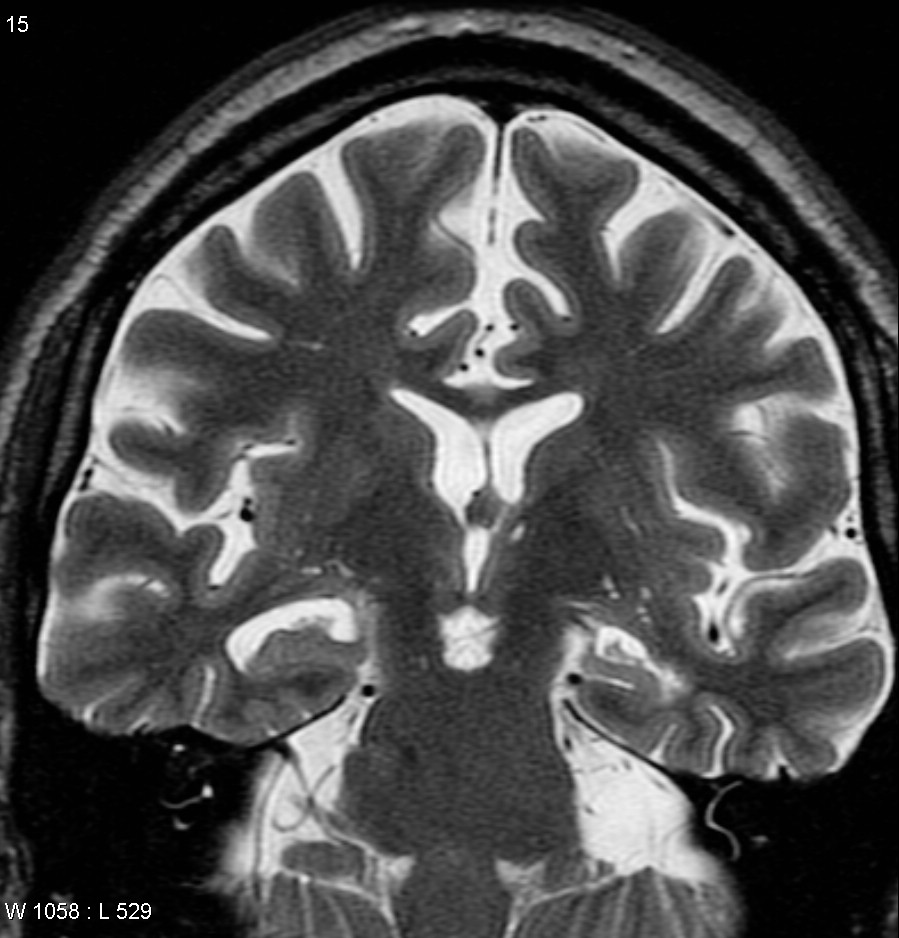

Демиелинизирующие заболевания мозга: МРТ изображения